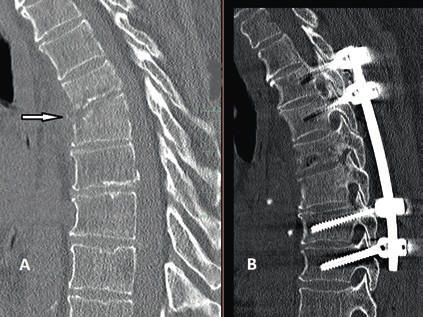

Prinzipiell richtet sich die Entscheidung, welche operative Versorgung durchgeführt wird, nach Ausmaß und Art der Verletzung. Für die Stabilisierung der dorsalen Säule reicht im Falle einer stabilen ventralen Säule die dorsale Instrumentierung aus. Hier gewährleisten dorsale Pedikelschrauben, die mit einem Stab verbunden sind, eine gute Wiederherstellung der Stabilität (Abb. 2). Im Falle einer instabilen ventralen Säule ist hingegen eine Implantation von Wirbelkörperersatz und eine dorsoventrale Segmentversteifung indiziert (Abb. 3). Die entwickelten minimalinvasiven Techniken – zum Beispiel die transkutane Pedikelschraubenimplantation oder der Wirbelkörperersatz durch endoskopische Thorakotomie – haben dazu geführt, dass das Wundgebiet und die operationsbedingte Gewebeschädigung reduziert werden und somit eine Belastungsreduktion für den Körper erzielt wird. Dieser Aspekt ist insbesondere bei älteren Patienten mit multiplen Begleiterkrankungen von Vorteil. Im Falle einer osteoporotischen Wirbelsäule werden die implantierten Pedikelschrauben zementiert (Abb. 4). Auch hier erlaubt die Entwicklung fenestrierter Schrauben eine optimale Möglichkeit der Zementapplikation.